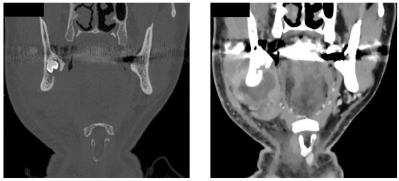

71歳の男性。顔面部の腫脹を主訴として来院した。右側顎下部に有痛性の腫脹を認める。初診時のエックス線写真、骨表示CT及び造影CTを示す。

顎下隙に認められるのはどれか。1つ選べ。